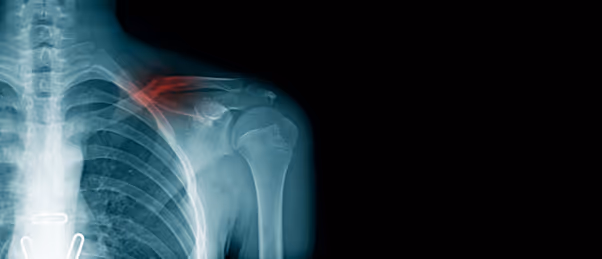

Chest radiography is an important imaging test used to routinely diagnose a broad range of diseases affecting the chest, including the heart and lungs. Chest X-rays can indicate conditions such as pneumonia, cancer and organ abnormalities. There is currently a universal shortage of radiologists while the demand for medical imaging, particularly CTs and MRIs, has risen exponentially.

In this study, chest X-ray images from 1529 in-hospital patients, emergency department patients and outpatients were examined by a deep learning AI tool that grouped each radiograph into one of two categories: “high-confidence normal” and “not high-confidence normal”, or normal and abnormal respectively. The deep learning algorithm was trained using approximately 600,000 chest radiographs.